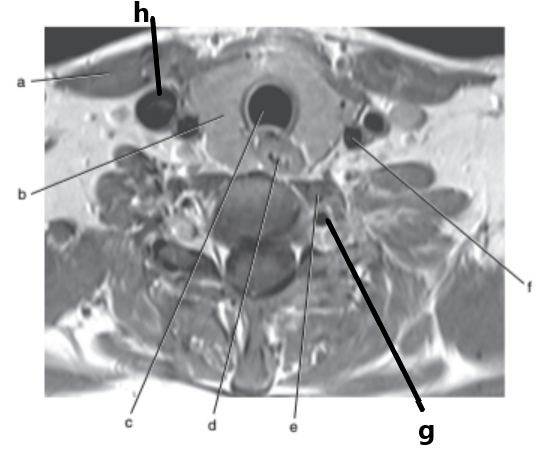

Internal jugular vein

Spinal cord

What imaging plane is this ?

transverse

Vertebral artery